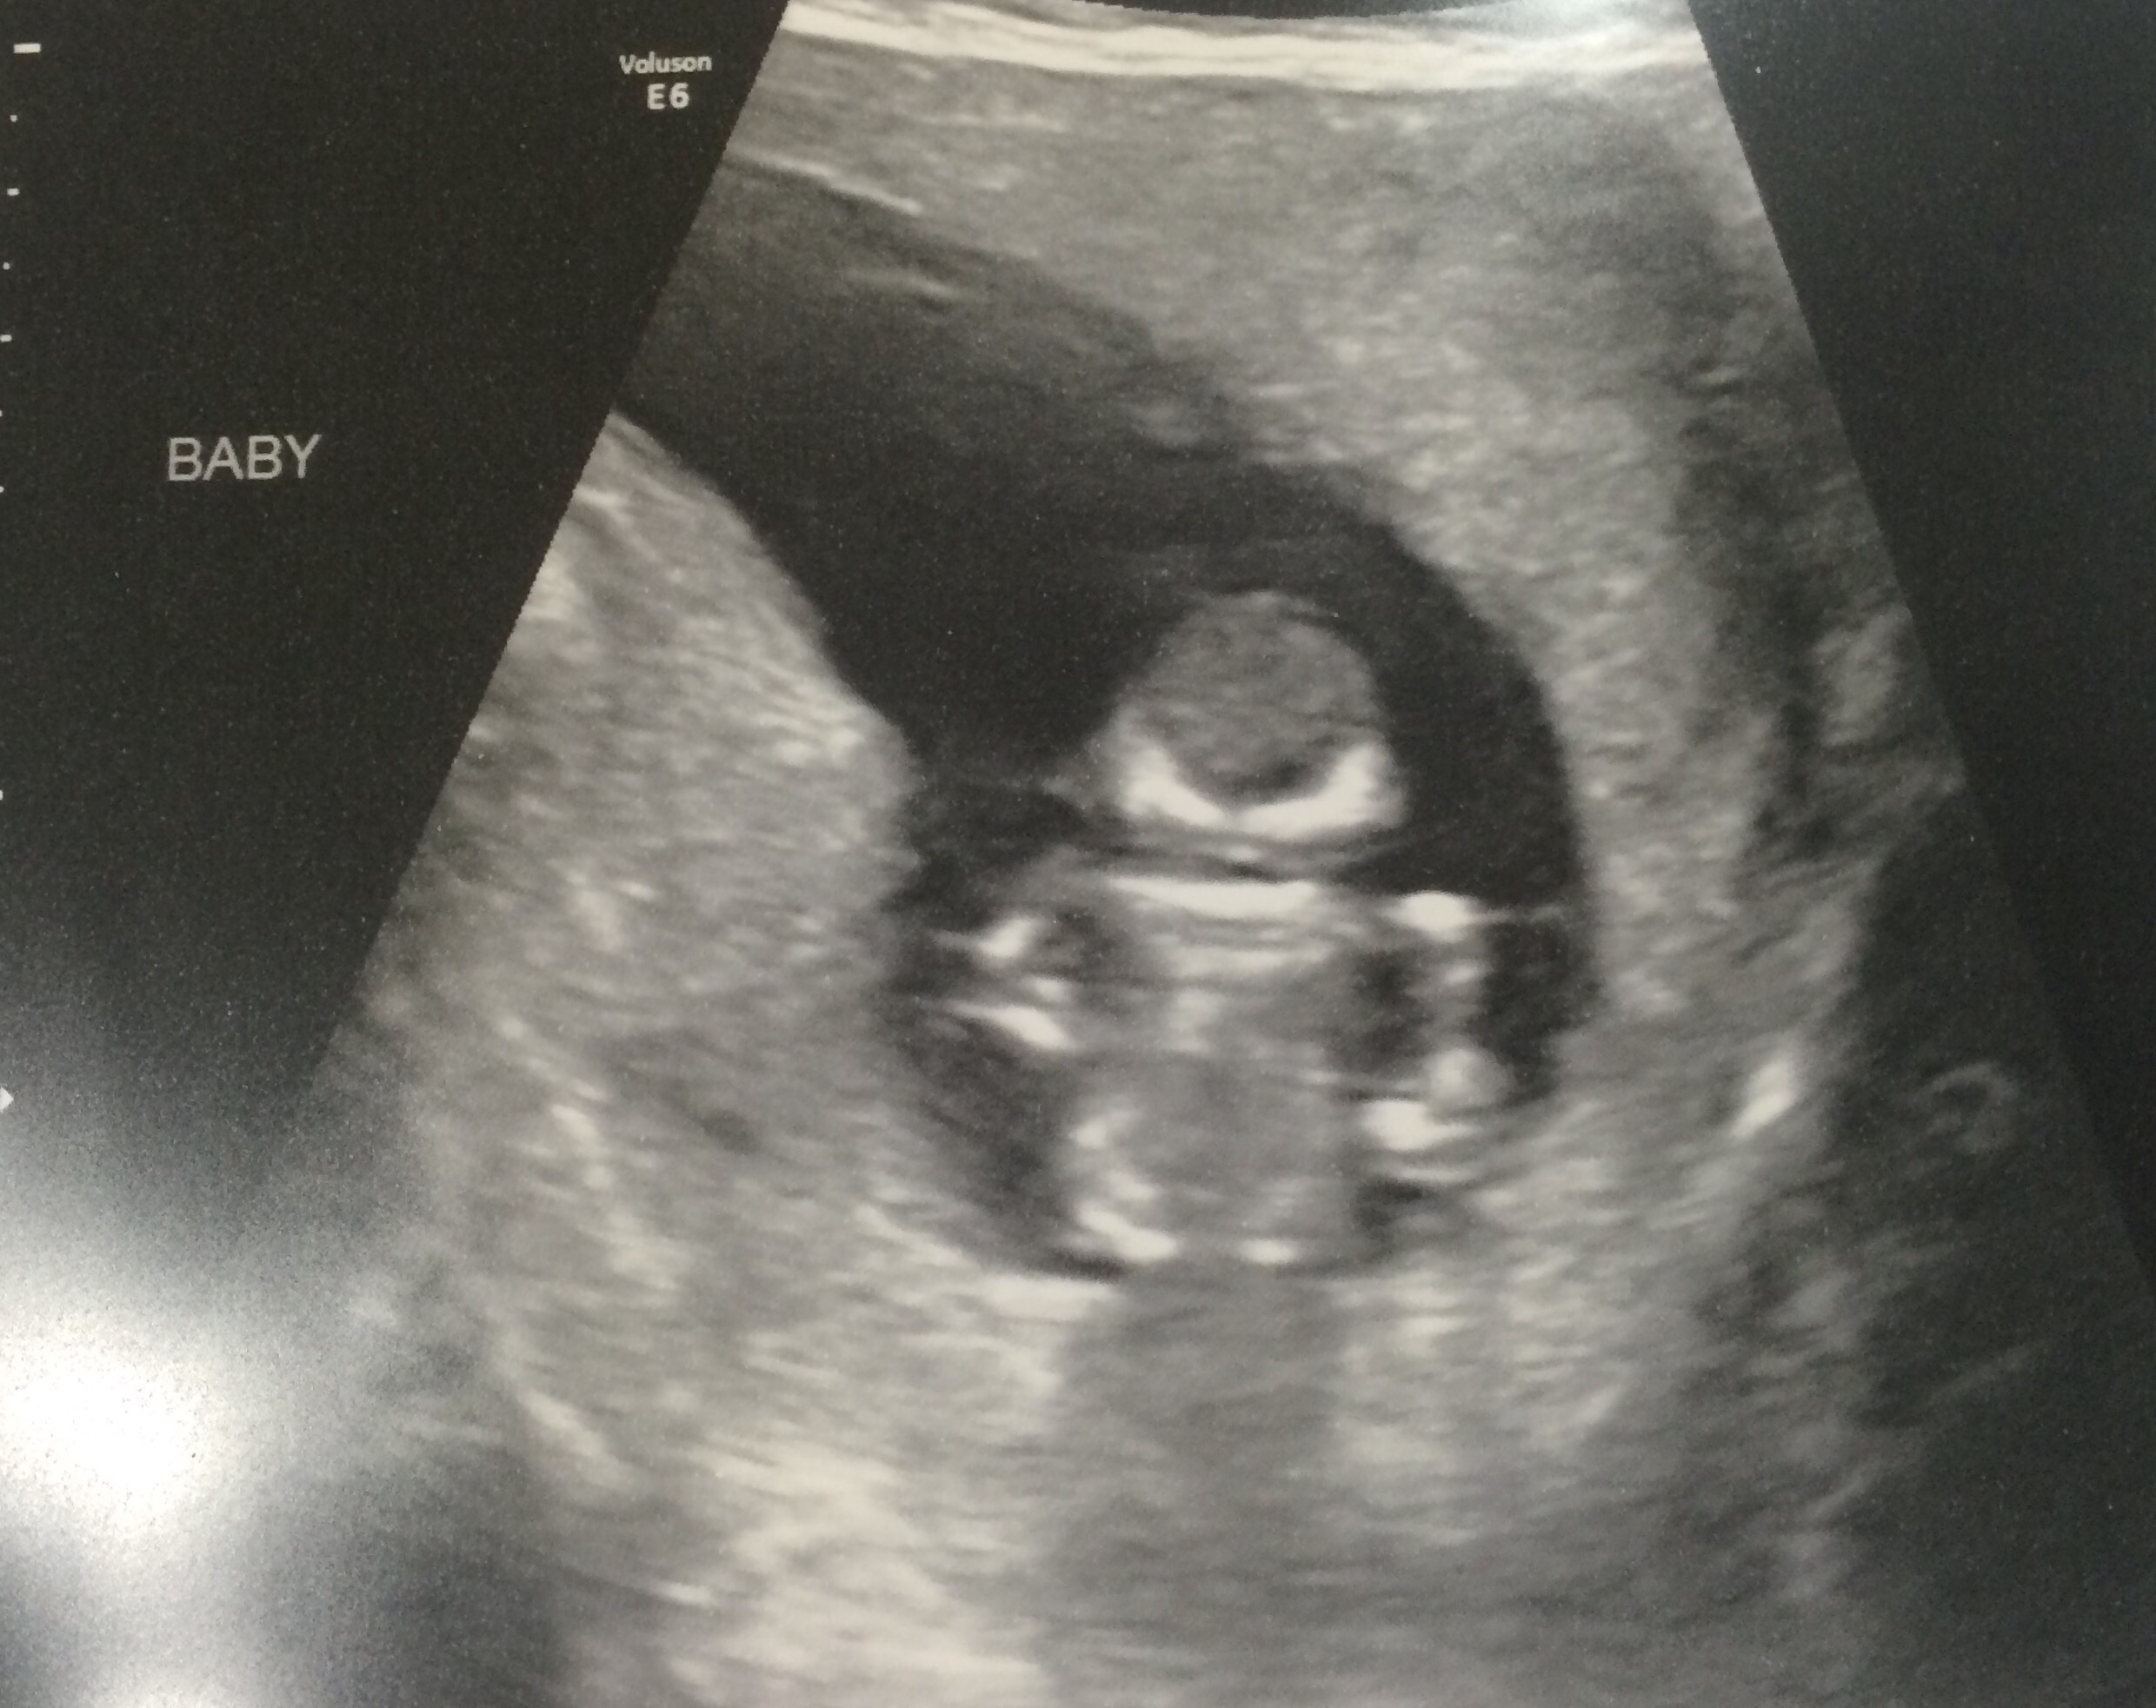

scw89 said:99% sure I'm carrying baby Iron Man....

Looks like Lego Iron Man to me.

I agree... lego iron man!

My thoughts as well. Let's hope it doesn't transform mid-delivery!